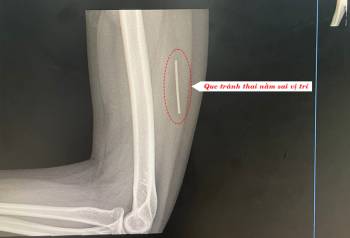

Chuyện 'lạ': que tránh thai ‘lạc’ trong... bắp tay